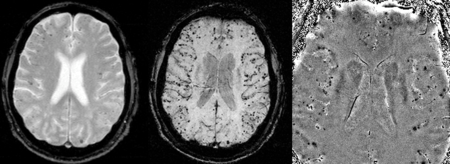

Vascular dementia and cerebral amyloid angiopathy (CAA)

Gradient recalled echo (GRE) imaging is the conventional way to detect hemorrhage in CAA, however SWI is a much more sensitive technique that can reveal many micro-hemorrhages that are missed on GRE images.[6] A conventional gradient echo T2*-weighted image (left, TE=20 ms) shows some low-signal foci associated with CAA. On the other hand, an SWI image (center, with a resolution of 0.5 mm x 0.5 mm x 2.0 mm, projected over 8mm) shows many more associated low-signal foci. Phase images were used to enhance the effect of the local hemosiderin build-up. An example phase image (right) with yet higher resolution of 0.25 mm x 0.25 mm x 2.0 mm shows a clear ability to localize multiple CAA-associated foci.